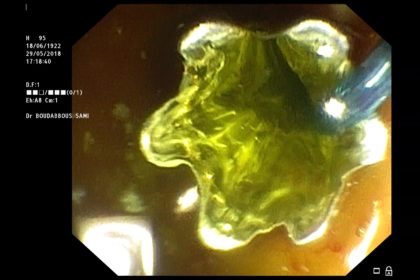

paradormirmejor.org height= »400″ /> cholangiogrtaphie rétrograde: image de sténose irrégulière.